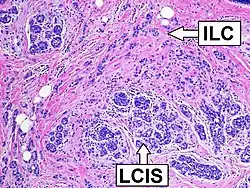

Histopathology of invasive lobular carcinoma (ILC), next to lobular carcinoma in situ (LCIS)

Histopathology of invasive lobular carcinoma (ILC), next to lobular carcinoma in situ (LCIS) -